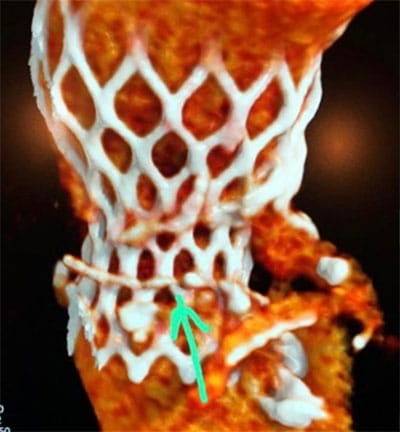

• High volume program with daily case averages of 10 CMR studies and 25-35 cardiac CTAs (50% coronary CTA, 30% structural, 20% other). Broad case complexity, including CAD, structural heart pathologies, congenital heart disease,  and implantable devices. Routine use of cutting edge technology, including T1/ECV mapping, quantitative perfusion, free-breathing CMR exam, artificial intelligence based CT analyses, CT-FFR, structural planning and simulation.